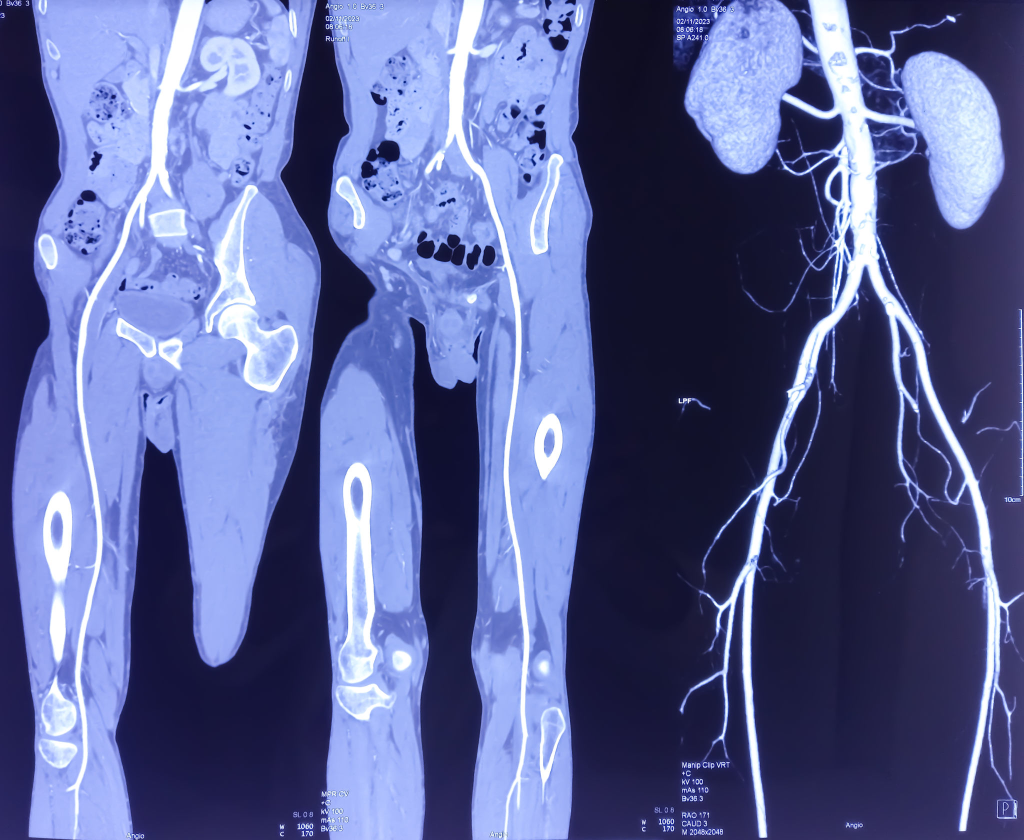

BT anjiyografi / MR anjiyo: infrarenal aorta + iliak darlık/oklüzyon

Radyografik özellikler

BT anjiyografi genellikle değerlendirme için en iyi yöntemdir. BT’nin mümkün olmadığı hastalarda, kontrastlı MR anjiyografi iyi bir seçenek olabilir

BT anjiyografi

Bu yöntem, stenoz ve tıkanıklığın yerinin doğrudan anatomik olarak görüntülenmesine olanak tanır. Ayrıca, iç organ arterlerini etkileyen eşlik eden tıkayıcı bir hastalığın varlığını, kollateralizasyonun tipini ve kapsamını ve stent greft yerleştirilmesine uygun en proksimal ve distal arter segmentlerinin seviyesini değerlendirmeye izin verir.